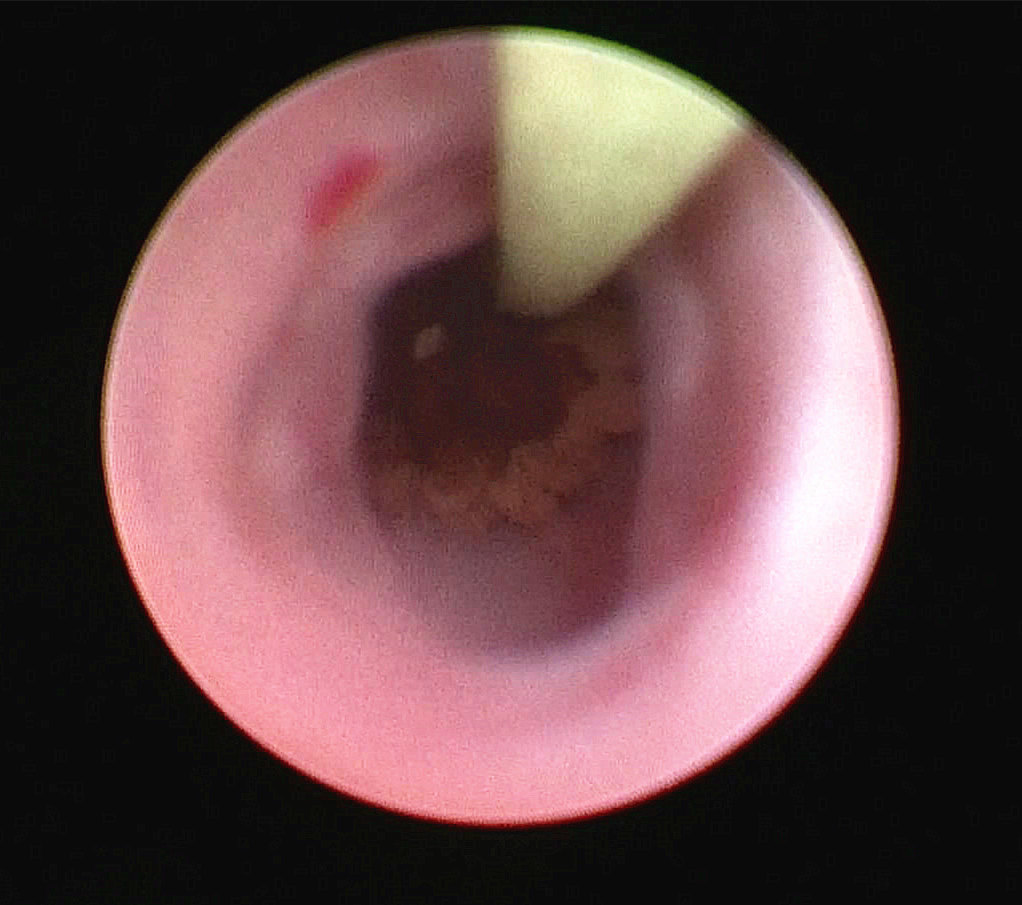

术中输尿管镜下发现右输尿管结石由于梗阻时间太长,已被息肉包裹,引起输尿管完全梗阻

予以钬激光将结石粉碎,完全恢复右输尿管的连续性,但由于就诊太晚,预后很差,日后血透治疗已不可避免